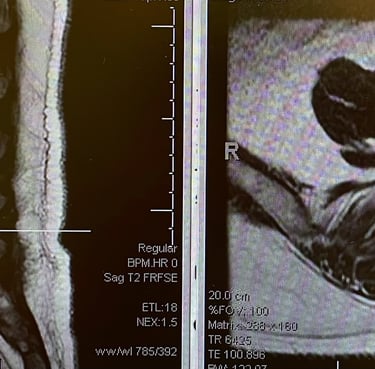

Focused on lumbar spine imaging excellence.

Spine Imaging

Precision in anterior and oblique views.